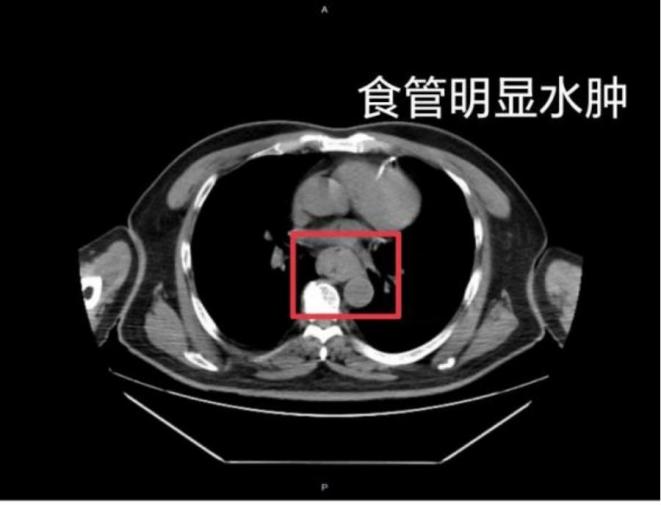

近日,福州一位網(wǎng)友也分享了自己因吃很燙的福鼎肉片導(dǎo)致嘔血,并查出食管水腫的經(jīng)歷。據(jù)網(wǎng)友回憶,“去廁所嘗試嘔吐時(shí),直接嘔出了血,一大口鮮血從嘴里噴出,總共吐了兩次”。CT結(jié)果顯示,他的食管全部水腫損傷。